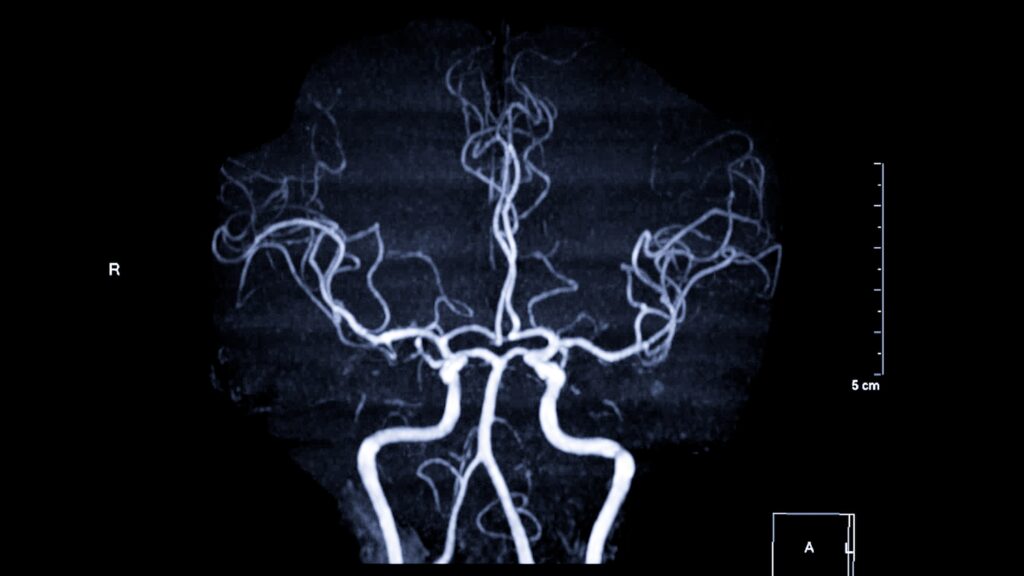

L’artère vertébrale irrigue des zones vitales du système nerveux comme le tronc cérébral, le cervelet et les régions postérieures du cerveau. Une atteinte, même minime, peut provoquer un AVC, un effondrement neurologique ou un décès rapide. Son trajet anatomique, profondément enfoui dans la colonne cervicale, la rend difficile à explorer. En contexte médico-légal, une lésion sur cette artère constitue un indice déterminant dans l’analyse d’une plaie pénétrante du cou, souvent révélateur d’une intention potentiellement létale.

Utilisée en médecine pour ses capacités d’imagerie dynamique, la fluoroscopie permet de suivre la circulation d’un agent de contraste à travers les vaisseaux. Elle met en évidence les fuites, sténoses ou occlusions caractéristiques d’un traumatisme vasculaire. Mais si elle offre une vue d’ensemble, sa résolution reste insuffisante pour examiner les lésions microscopiques.

Pour franchir cette limite, les chercheurs recourent à la micro-tomographie, une technique d’imagerie à très haute résolution. L’échantillon est tourné sur lui-même pendant la prise de milliers d’images radiographiques, qui sont ensuite reconstruites en un modèle 3D numérique. Ce procédé révèle des détails invisibles autrement comme des déchirures de la paroi artérielle, thrombus, dissections ou ruptures partielles. Ces reconstructions offrent la possibilité de réaliser des dissections virtuelles sous différents angles, sans altérer le corps, et en garantissant une reproductibilité précieuse en contexte judiciaire.